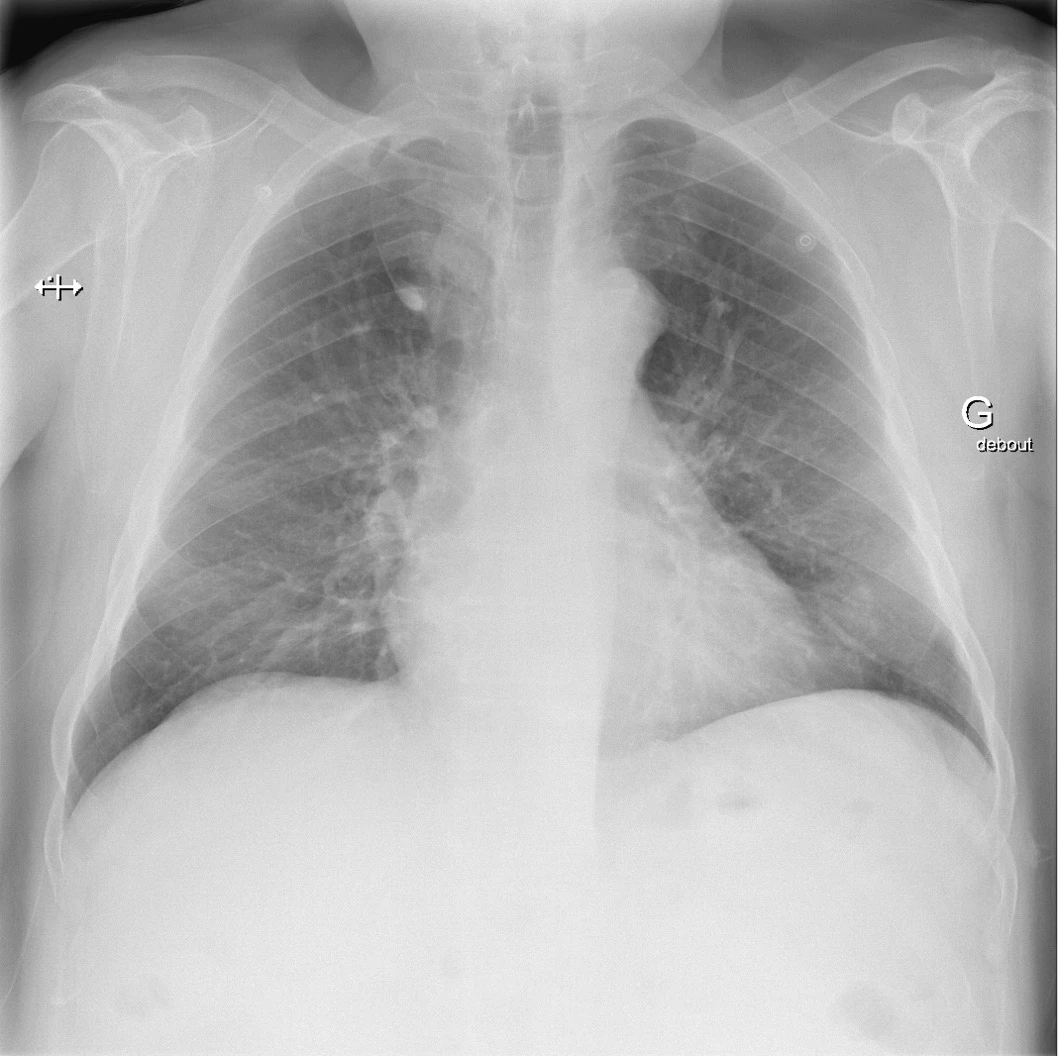

Masse dans le lobe supérieur droit

Le lobe azygos est une anomalie congénitale, ou variante anatomique. Bien que rare (il se retrouve chez environ 1% de la population avec un ratio homme : femme de 2 : 1 et sur 0.4 % des radiographies thoraciques), cette variante doit être connue de la ou du clinicien·ne car elle peut être confondue avec un néoplasie pulmonaire, un abcès ou une bulle d’emphysème voir un pneumothorax.

Les signes radiologiques classiques sont :

1. Au niveau paratrachéal droit :

• Une image de larme par la présence de la veine azygos déplacée latéralement et se retrouvant piégée dans le parenchyme pulmonaire et les plis de la plèvre

• Une image de virgule inversée par la veine qui indente le lobe supérieur droit et crée une scissure accessoire (pli de la plèvre pariétale et viscérale, mésoazygos)

2. À la portion supérieure de la fissure : une opacité triangulaire, le trigone pariétal, qui est du tissu extrapulmonaire pris en sandwich lors de la migration de la veine azygos.

3. Au bord inférieur de la bande paratrachéale droite : le renflement habituellement présent en raison du passage de la veine azygos à l’angle trachéobronchique n’est pas visible.